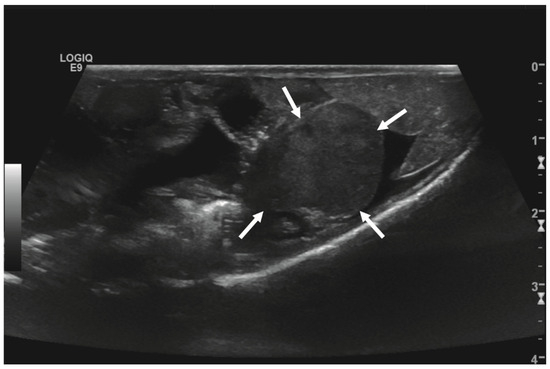

Initial diagnostic methods included parasitological fecal examination, radiography, and ultrasonography. The animal owner declined a blood examination due to financial restrictions. Microscopic fecal examination at 100× magnification revealed a high infestation of oxyurids (>20 eggs per field of view) and a low-grade flagellate infestation. Under manual restraint, dorsoventral and horizontal beam lateral radiographic projections were performed (Figure 1; digital X-ray; detector system: Fujifilm Console Advance DR-ID 300 CL, Fujifilm Europe GmbH, Düsseldorf, Germany; tube system: Gierth X-ray International GmbH, Riesa, Germany; film focus distance FFD 60 cm, 50 kV, 5 mAs). The lateral radiograph was insufficient for any evaluation due to a technical issue. On the dorsoventral view, the medial right coelom was filled with soft-tissue material and hypodense areas (moderately filled gastrointestinal tract and gastrointestinal gas). Mineral opacities were visible in the left coelom, indicating deposits of foreign material (sand or similar anorganic substrate) in the large intestine. Both lung fields were visible on the dorsoventral radiograph, though superimpositions with the gastrointestinal tract did not allow a clear evaluation of the entire lung field size. No distinct intracoelomic lesion was determinable upon radiography. Ultrasonographic examination under manual restraint and in dorsal recumbency (Micro curved array transducer, 5–9 MHz; Vivid 7 Dimension; GE Healthcare GmbH, Solingen, Germany) with transverse and longitudinal views from the ventral coupling site showed an approximately 2 × 1.5 cm round-shaped, intracoelomic mass located in the middle third of the medial right coelom. The structure was surrounded by intestinal and fat body tissue (Figure 2). However, the mass showed good vascularization, and demarcation to surrounding tissue was clearly feasible (Figure 3). No other abnormalities of coelomic organs were visualized during the ultrasound examination.

Figure 2. Transverse ultrasonographic image of the medial right coelom in a bearded dragon acquired with a 5 to 9 MHz micro curved array transducer (penetration depth 3 cm; frequency 15 MHz) showing an approximately 2 × 1.5 cm round-shaped, irregular intracoelomic mass (arrows). Additionally, the gastrointestinal tract (medial, here: to the left of the mass) and fat body (lateral, here: to the right of the mass) are visible and closely related to the mass.